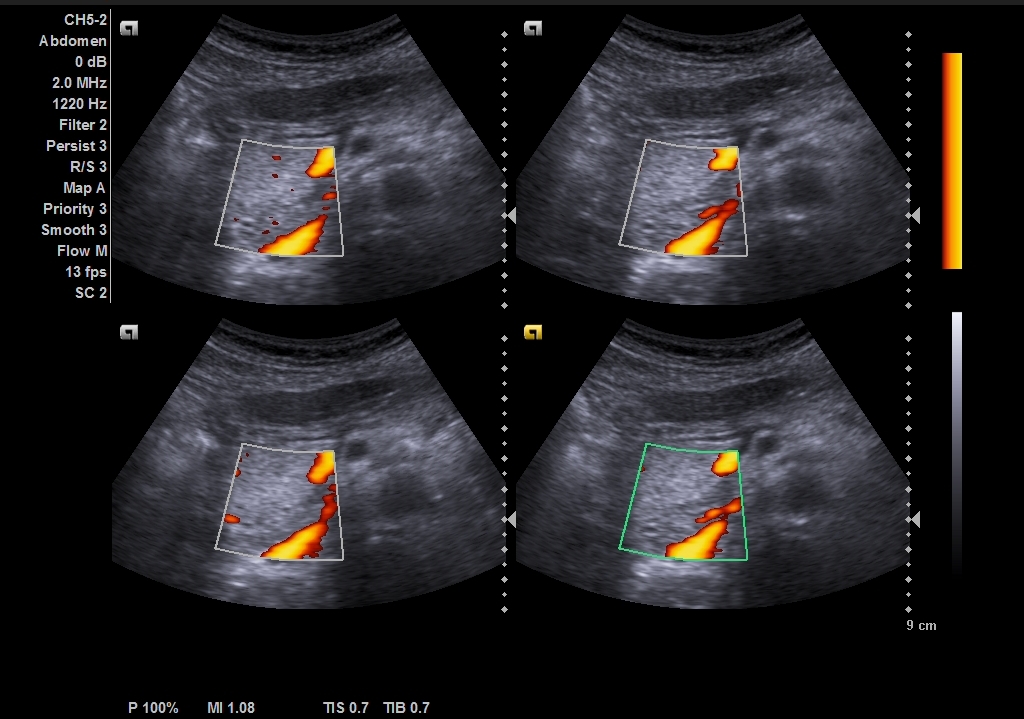

Student Image Challenge 64August 18, 2020Xiang Fei – SpeakerSeptember 7, 2020 Student Image Challenge 65 Student Image Challenge #65 1 / 1 Student Image Challenge #65 What is your diagnosis based on this US image of an asymptomatic patient? Pancreatic cancer Acute pancreatitis A normal image of the pancreas Chronic pancreatitis Pancreas divisum Incorrect ....Please see the correct answer highlighted Correct: A normal image of the pancreas The ventral pancreas has a triangular shape and it is slightly hypoechoic, which could simulate a tumor. Your score isThe average score is 25% LinkedIn Facebook VKontakte 0% Restart quiz Case courtesy of Prof Adrian Saftoiu EFSUMBAdmin Related postsStudent Image Challenge 112Read more Comments are closed.